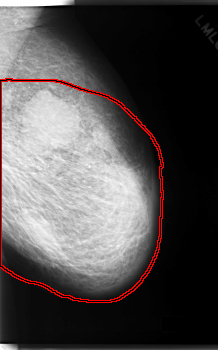

C_0055_1.LEFT_CC

LEFT_CC LINES 6040 PIXELS_PER_LINE 3552 BITS_PER_PIXEL 12 RESOLUTION 50 OVERLAY

FILE: C_0055_1.LEFT_CC.OVERLAY

TOTAL_ABNORMALITIES 1

ABNORMALITY 1

LESION_TYPE CALCIFICATION TYPE PLEOMORPHIC DISTRIBUTION SEGMENTAL

ASSESSMENT 5

SUBTLETY 5

PATHOLOGY MALIGNANT

TOTAL_OUTLINES 1

BOUNDARY